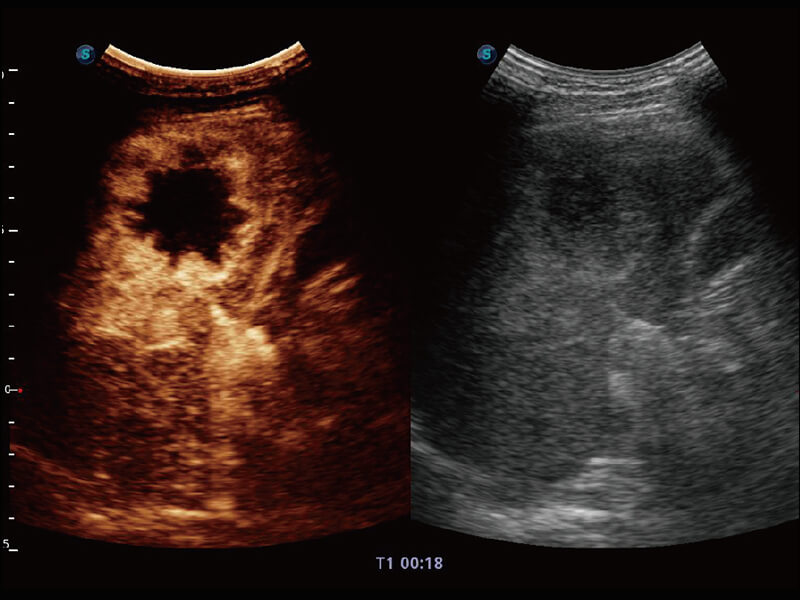

成像功能

性能优异的硬件架构,极大提升超声系统的运行效率和数据处理能力。相比以往超声成像系统,Wis+平台为您带来极快的响应速度和成像帧频,提升检查流畅度。

S60探头工艺,从前端信号处理每一个环节采集无损声学数据,真实还原组织原貌,再现解剖细节。